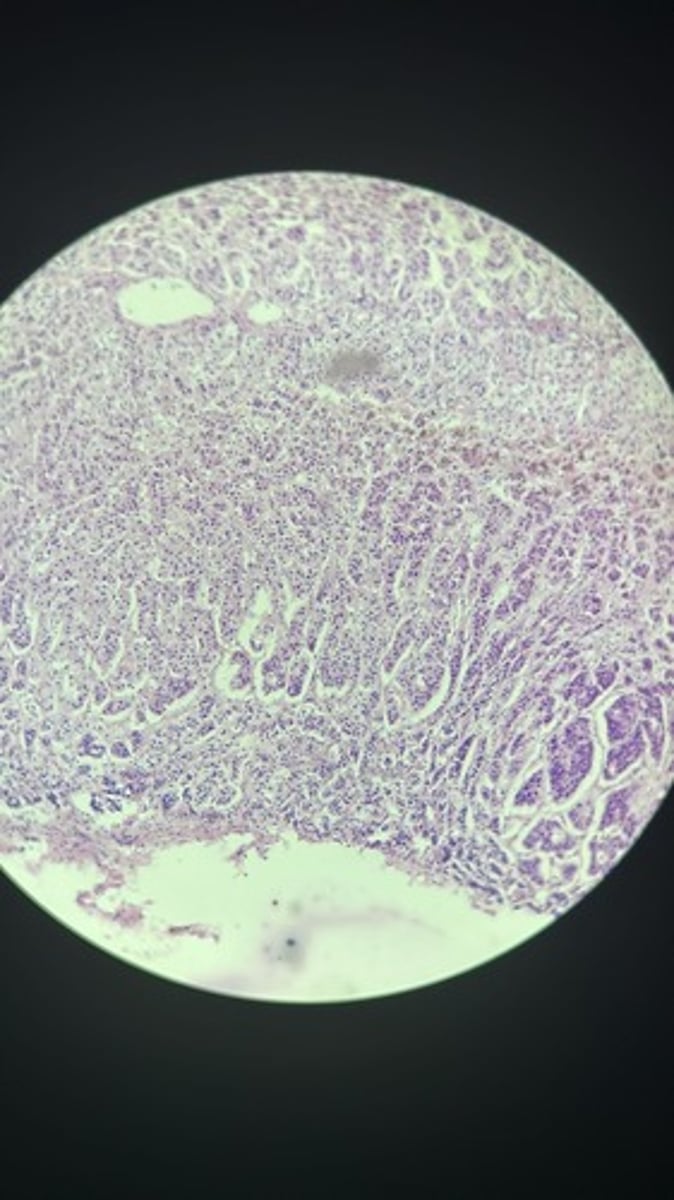

Thyroid gland HE

Thyroid gland HE

Thyroid gland HE

Thyroid HE